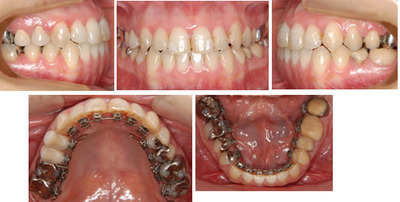

来院時の写真

治療中の写真

装置を外す直前の写真です。

歯を抜かずに治療できました。

表側に一切の装置を装着することはありませんでした。

アンカースクリュウなどは使用していません。

上顎前歯を前方に傾斜する事で改善しました。非抜歯、リンガルブラケットで矯正治療をおこないました。

治療に使用した装置 : リンガルブラケット

過去にう蝕の治療痕が多くあります。矯正治療中は毎回来院時にブラッシング指導、スケーリングを行います。

治療期間 : 24か月